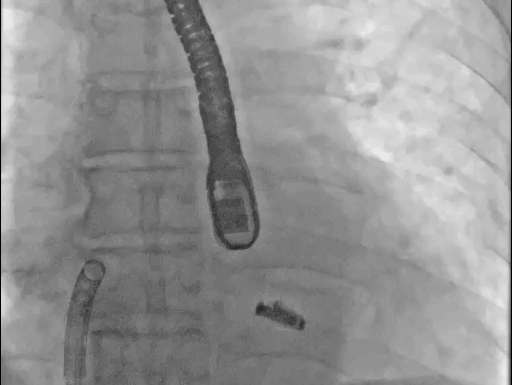

手术过程:

手术于全麻下进行,采用股静脉房间隔途径,房间隔穿刺后置入外径22F导管鞘及夹合器输送系统,在TEE引导下,将1枚长宽型号的KoKaClip®夹合器顺利植入到二尖瓣A2/P2区,夹合器位置稳定。彩色多普勒超声显示微少量残余分流,整体反流量改善2级以上,肺静脉多普勒波形由反向恢复正常。多切面证实夹合组织充分,双孔化形成,遂移除器械输送系统,手术顺利完成。

术前

术后